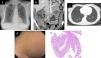

We present the case of a 47-year-old female worker of an elderly nursing home with no previous significant medical history was admitted to the emergency room. She reported 10 days of right lower quadrant abdominal pain, high fever (maximum 39.5°C) and non-bloody diarrhea. The patient did not report any respiratory symptoms. No other family members were affected. Two nasopharyngeal and oropharyngeal swab specimens performed before admission had been negative for SARS-CoV-2. Respiratory auscultation was strictly normal, and pain was noted on the palpation of the right lower abdominal quadrant. Blood test showed markedly increased inflammatory parameters (leukocytes, D-Dimer, ferritin C-reactive protein). Chest X-ray was normal (Fig. 1a). Abdominal CT scan showed inflammatory signs in the distal ileum (Fig. 1b). The pulmonary images of the abdominal CT scan were normal (Fig. 1c).

Ileocolonoscopy was performed eleven days after because of the pandemic situation and the recommendation by our infectiology department of avoid the colonic preparation to prevent the possible risk of fecal SARS-CoV-2 elimination and the contagious to the medical team (currently this fact is not proved). No mucosal changes were found in the ileocolonic mucosa (Fig. 1d). Biopsies were taken and histology study showed no significant changes (Fig. 1e). NAAT of SARS-CoV-2, intestinal bacteria, viruses and parasites (Gastrointestinal panel Filmarray®, Biomerieux France) were performed being positive for SARS-CoV-2 and negative for Salmonella spp., Shigella spp., Yersinia enterocolitica, Aeromonas spp., Vibrio spp., Plesiomonas shigelloides, Clostridioides difficile, Campylobacter spp., Cryptosporidium spp., Entamoeba histolytica, Giardia intestinalis, Cyclospora cayetanensis, norovirus, astrovirus, sapovirus, adenovirus and rotavirus. At that time, serology was performed and both SARS-CoV-2 IgM+IgA and IgG antibodies were positive (Vircell SL®, Spain).